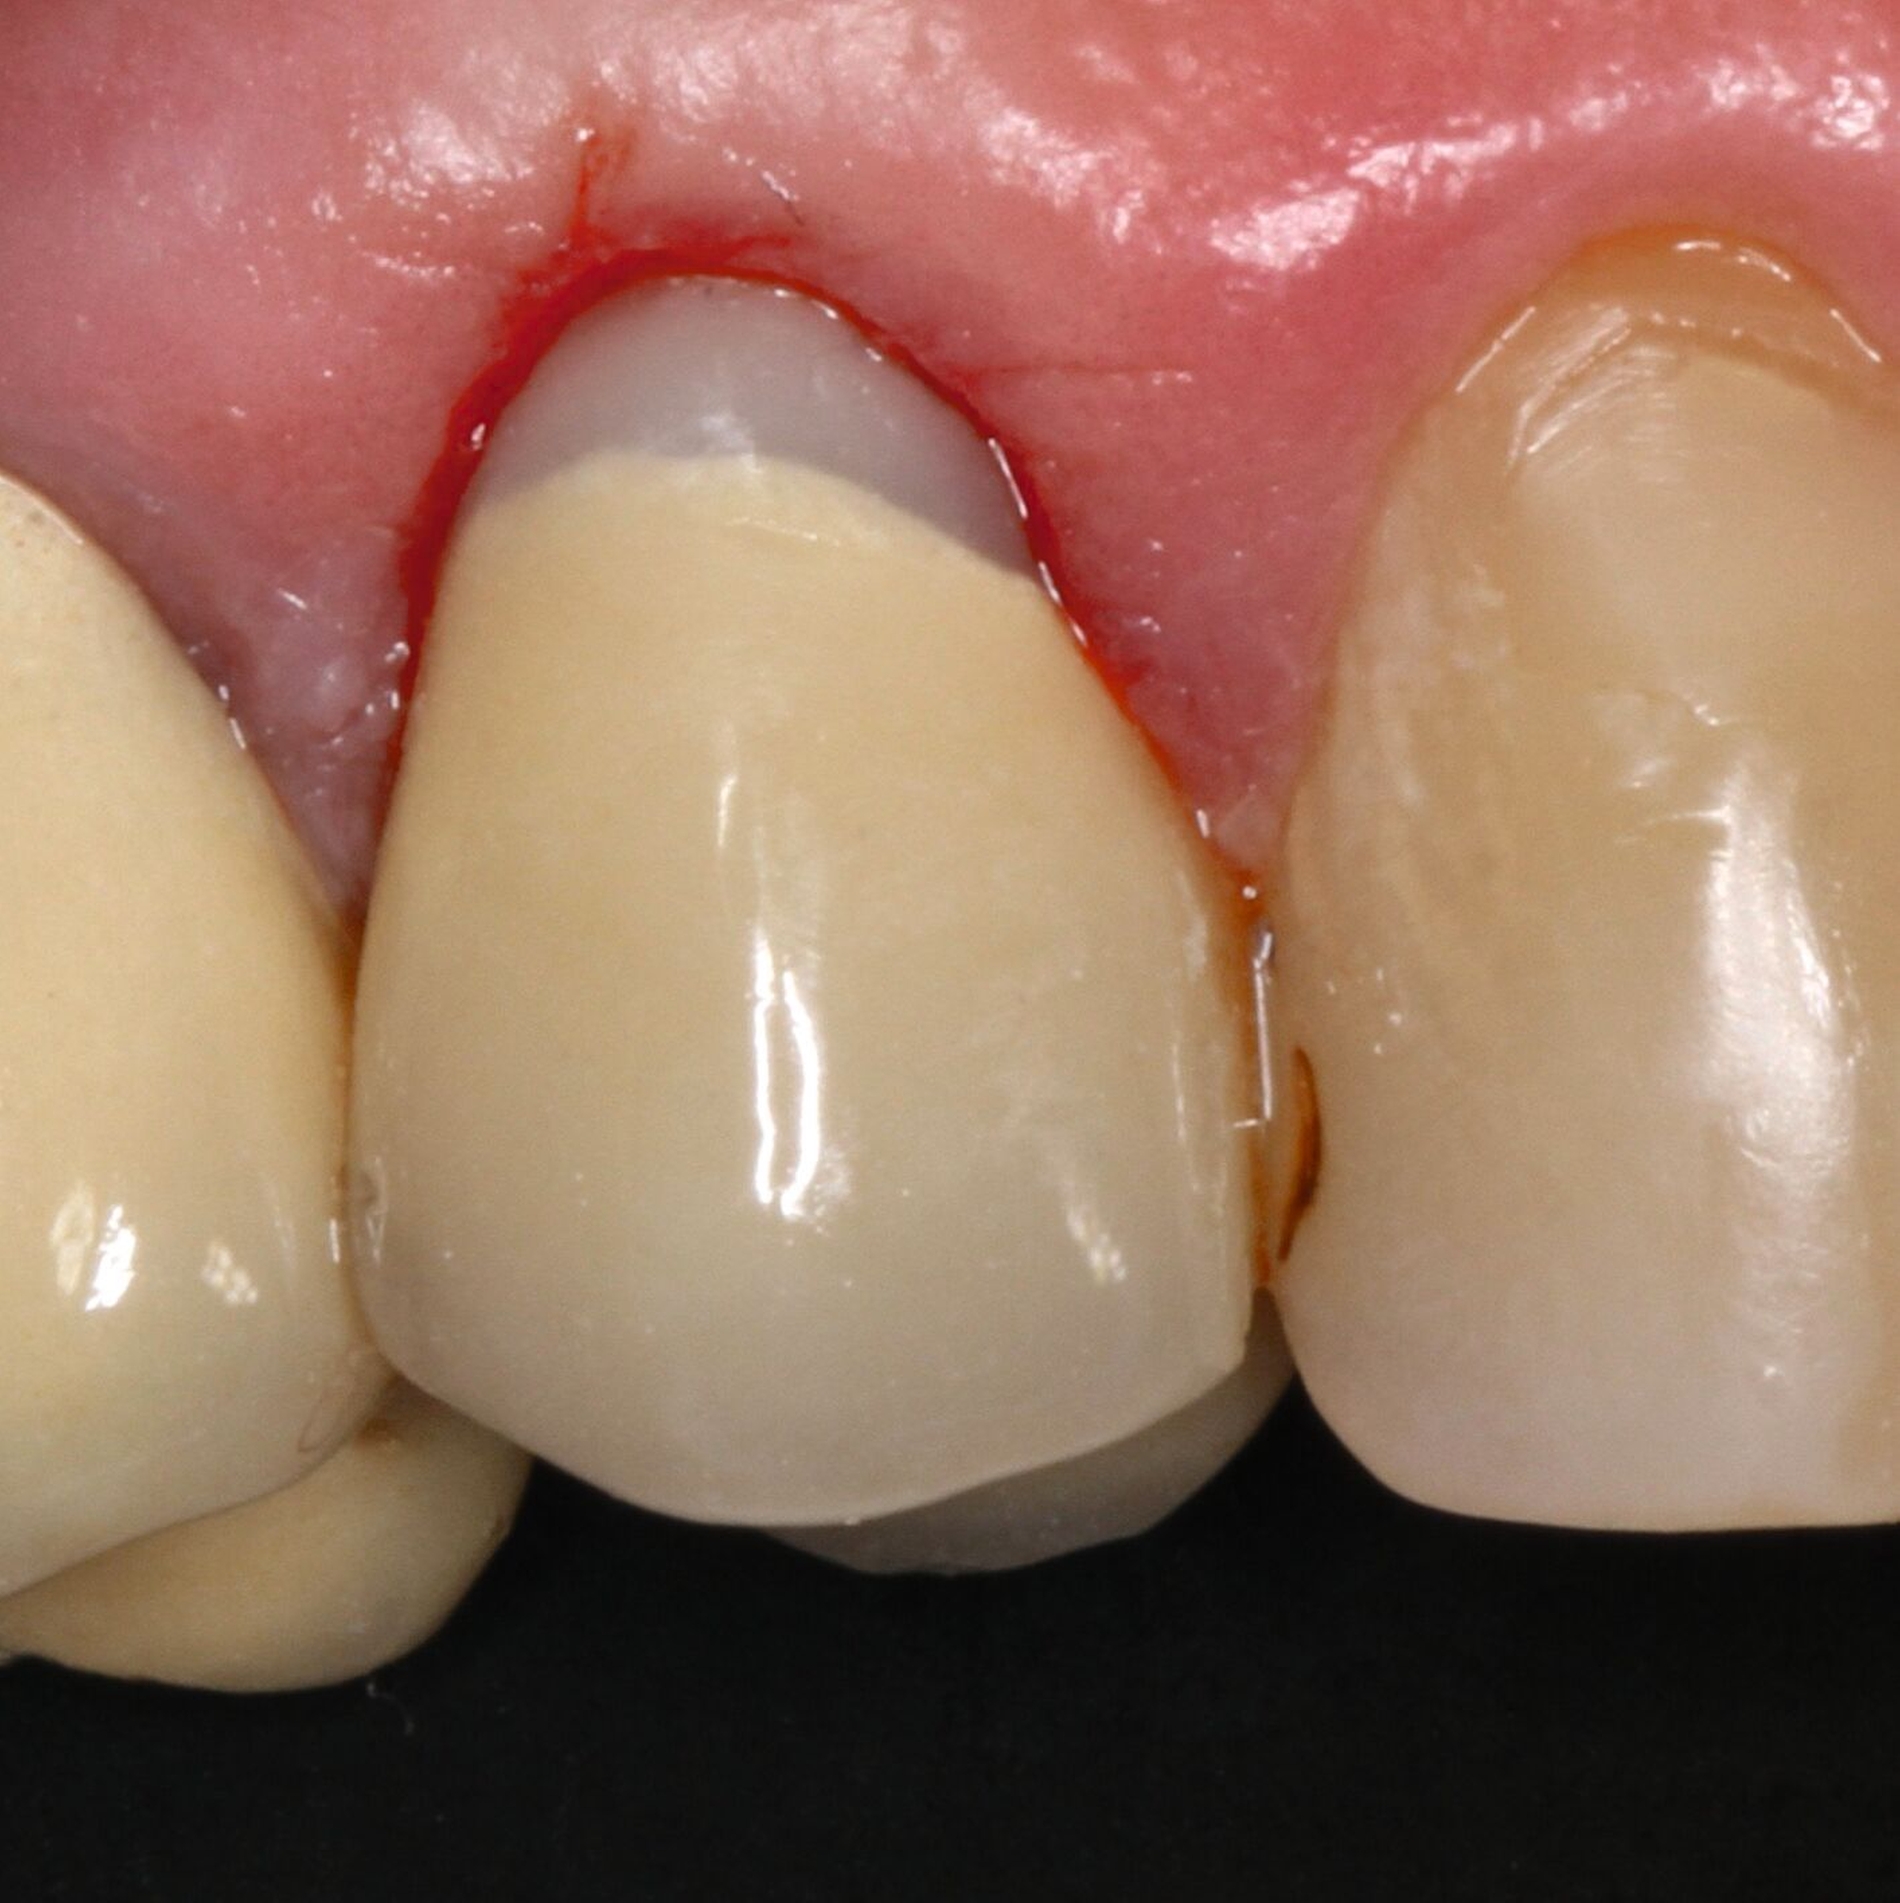

Für die restaurative Therapie von Zahn 22 wurde die alte Stiftkrone entfernt und die Stiftbohrung an die neue Indikation angepasst (Abbildungen 5a und 5b). Die Zahnkrone wurde dabei in drei Phasen wiederhergestellt: adhäsives Zementieren eines konfektionierten Glasfaserstifts, Stumpfaufbau und Modellation einer direkten Kompositkrone mit Silikonschlüssel, Frontzahnmatrize für komplexe Situationen und Schneepflugtechnik (Abbildungen 5c bis 5e) [Urkande et al., 2023; Amaro et al., 2021; Frese, 2020; Mannocci et al., 2002; Dimitrouli et al., 2011; Opdam et al., 2003]. Im Röntgenkontrollbild zeigt sich ein suffizienter Stiftaufbau (Abbildung 6).

-> Bei der Schneepflugtechnik wird eine dünne Schicht fließfähiges Komposit ohne Lichtpolymerisation auf die Zahn- oder Restaurationsoberfläche aufgetragen, ein mittelvisköses Komposit darüber adaptiert und beides zusammen polymerisiert. Ziele dieser Methode sind eine blasenfreie Adaptation des Komposits an die Zahnoberfläche sowie eine homogene Restauration [Opdam et al., 2003].